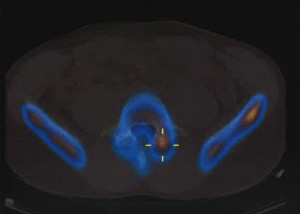

SPECT-EspondilolisisSPECT-EspondilolisisLa espondilolisis se define como un defecto óseo en la pars interarticular del arco vertebral. Se presenta una debilidad o fractura en uno de los puentes óseos que conecta las articulaciones facetarias. Este defecto o bien puede ser asintomático o asociado con un significativo dolor lumbar. Esta condición está presente en hasta un 6% de la población, sin embargo sólo el 10-15% de las personas desarrollará síntomas. Aunque la etiología de esta lesión todavía no está clara, se ha demostrado que existen factores de riesgo hereditarios y adquiridos, con una mayor prevalencia en hombres y atletas que participan en ciertos deportes de alto riesgo. La espondilolisis es, en efecto, una causa común de dolor lumbar en los atletas preadolescentes y adolescentes y en particular presenta un problema clínico en esta población. Ocurre con mayor frecuencia en las personas que participan en algunas actividades que parecen suponer un estrés inusual en su columna lumbar.

Desafortunadamente, se realizan diagnósticos erróneos de espondilólisis. Un factor de complicación en las primeras etapas de la enfermedad que conduce a un diagnóstico erróneo es el hecho de que las radiografías simples, incluso las oblicuas, pueden no ser útiles en la etapa de fractura por sobrecarga. Otras técnicas de imagen, como la gammagrafía ósea, posiblemente, la resonancia magnética o Tomografía computarizada de emisión monofotónica (SPECT) deben ser utilizadas al inicio del proceso de diagnóstico. En el ámbito de la atención primaria, el diagnóstico precoz de elemento de participación posterior relacionado con el dolor lumbar, ya sea en la etapa de la fractura por sobrecarga del pars o por espondilolisis temprana, puede prevenir la progresión de la enfermedad y evitar la necesidad de una intervención quirúrgica.